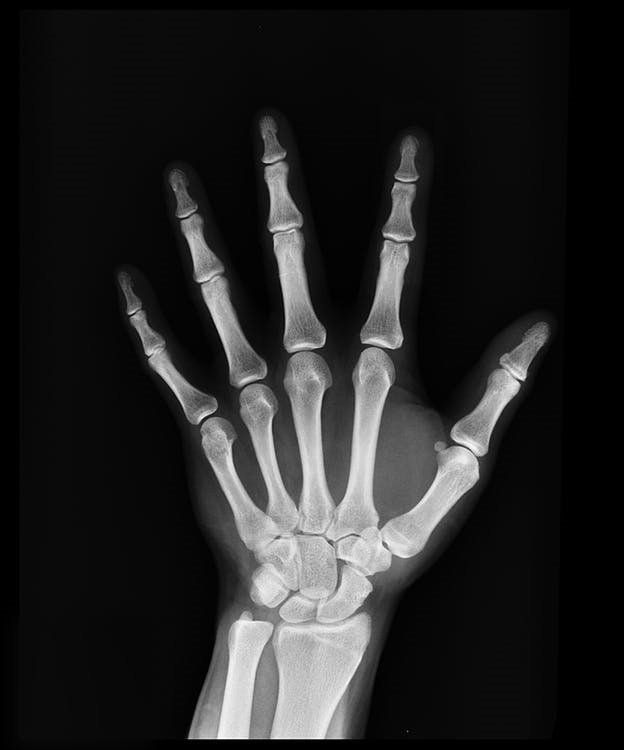

Handtherapie

Unsere Hand hat auf kleinsten Platz viele Strukturen, wie Knochen, Muskeln, Sehnen und Nerven. Durch die Überforderung unserer Hände kann sich diese geordnete und gut funktionierende Struktur in krankhafte Symptome verändern. Gleiches gilt auch bei Verletzung unserer Hände und Finger. Auch bei Unfällen der Schulter, Oberarme, Ellbogen und Unterarme kann es passieren, dass unsere Hände und Finger zu schmerzen beginnen. Dadurch entstehen auch häufig Fehlgefühle bis hin zum Taubheitsgefühl. Wegen eventueller Nervenschädigung oder Nervenquetschung kommt es auch häufig zu Bewegungseinschränkungen.

In der Handtherapie werden die verschiedenen Erkrankungen der Hand gezielt behandelt. Dadurch werden Folgeschäden, Fehlhaltungen, Ausweichbewegungen, Bindegewebsverklebungen und Schmerzen vorgebeugt. Das Ziel ist hier, die bestmögliche Beweglichkeit und Funktionsfähigkeit im Alltag, Beruf, Sport und Freizeit zu erreichen.